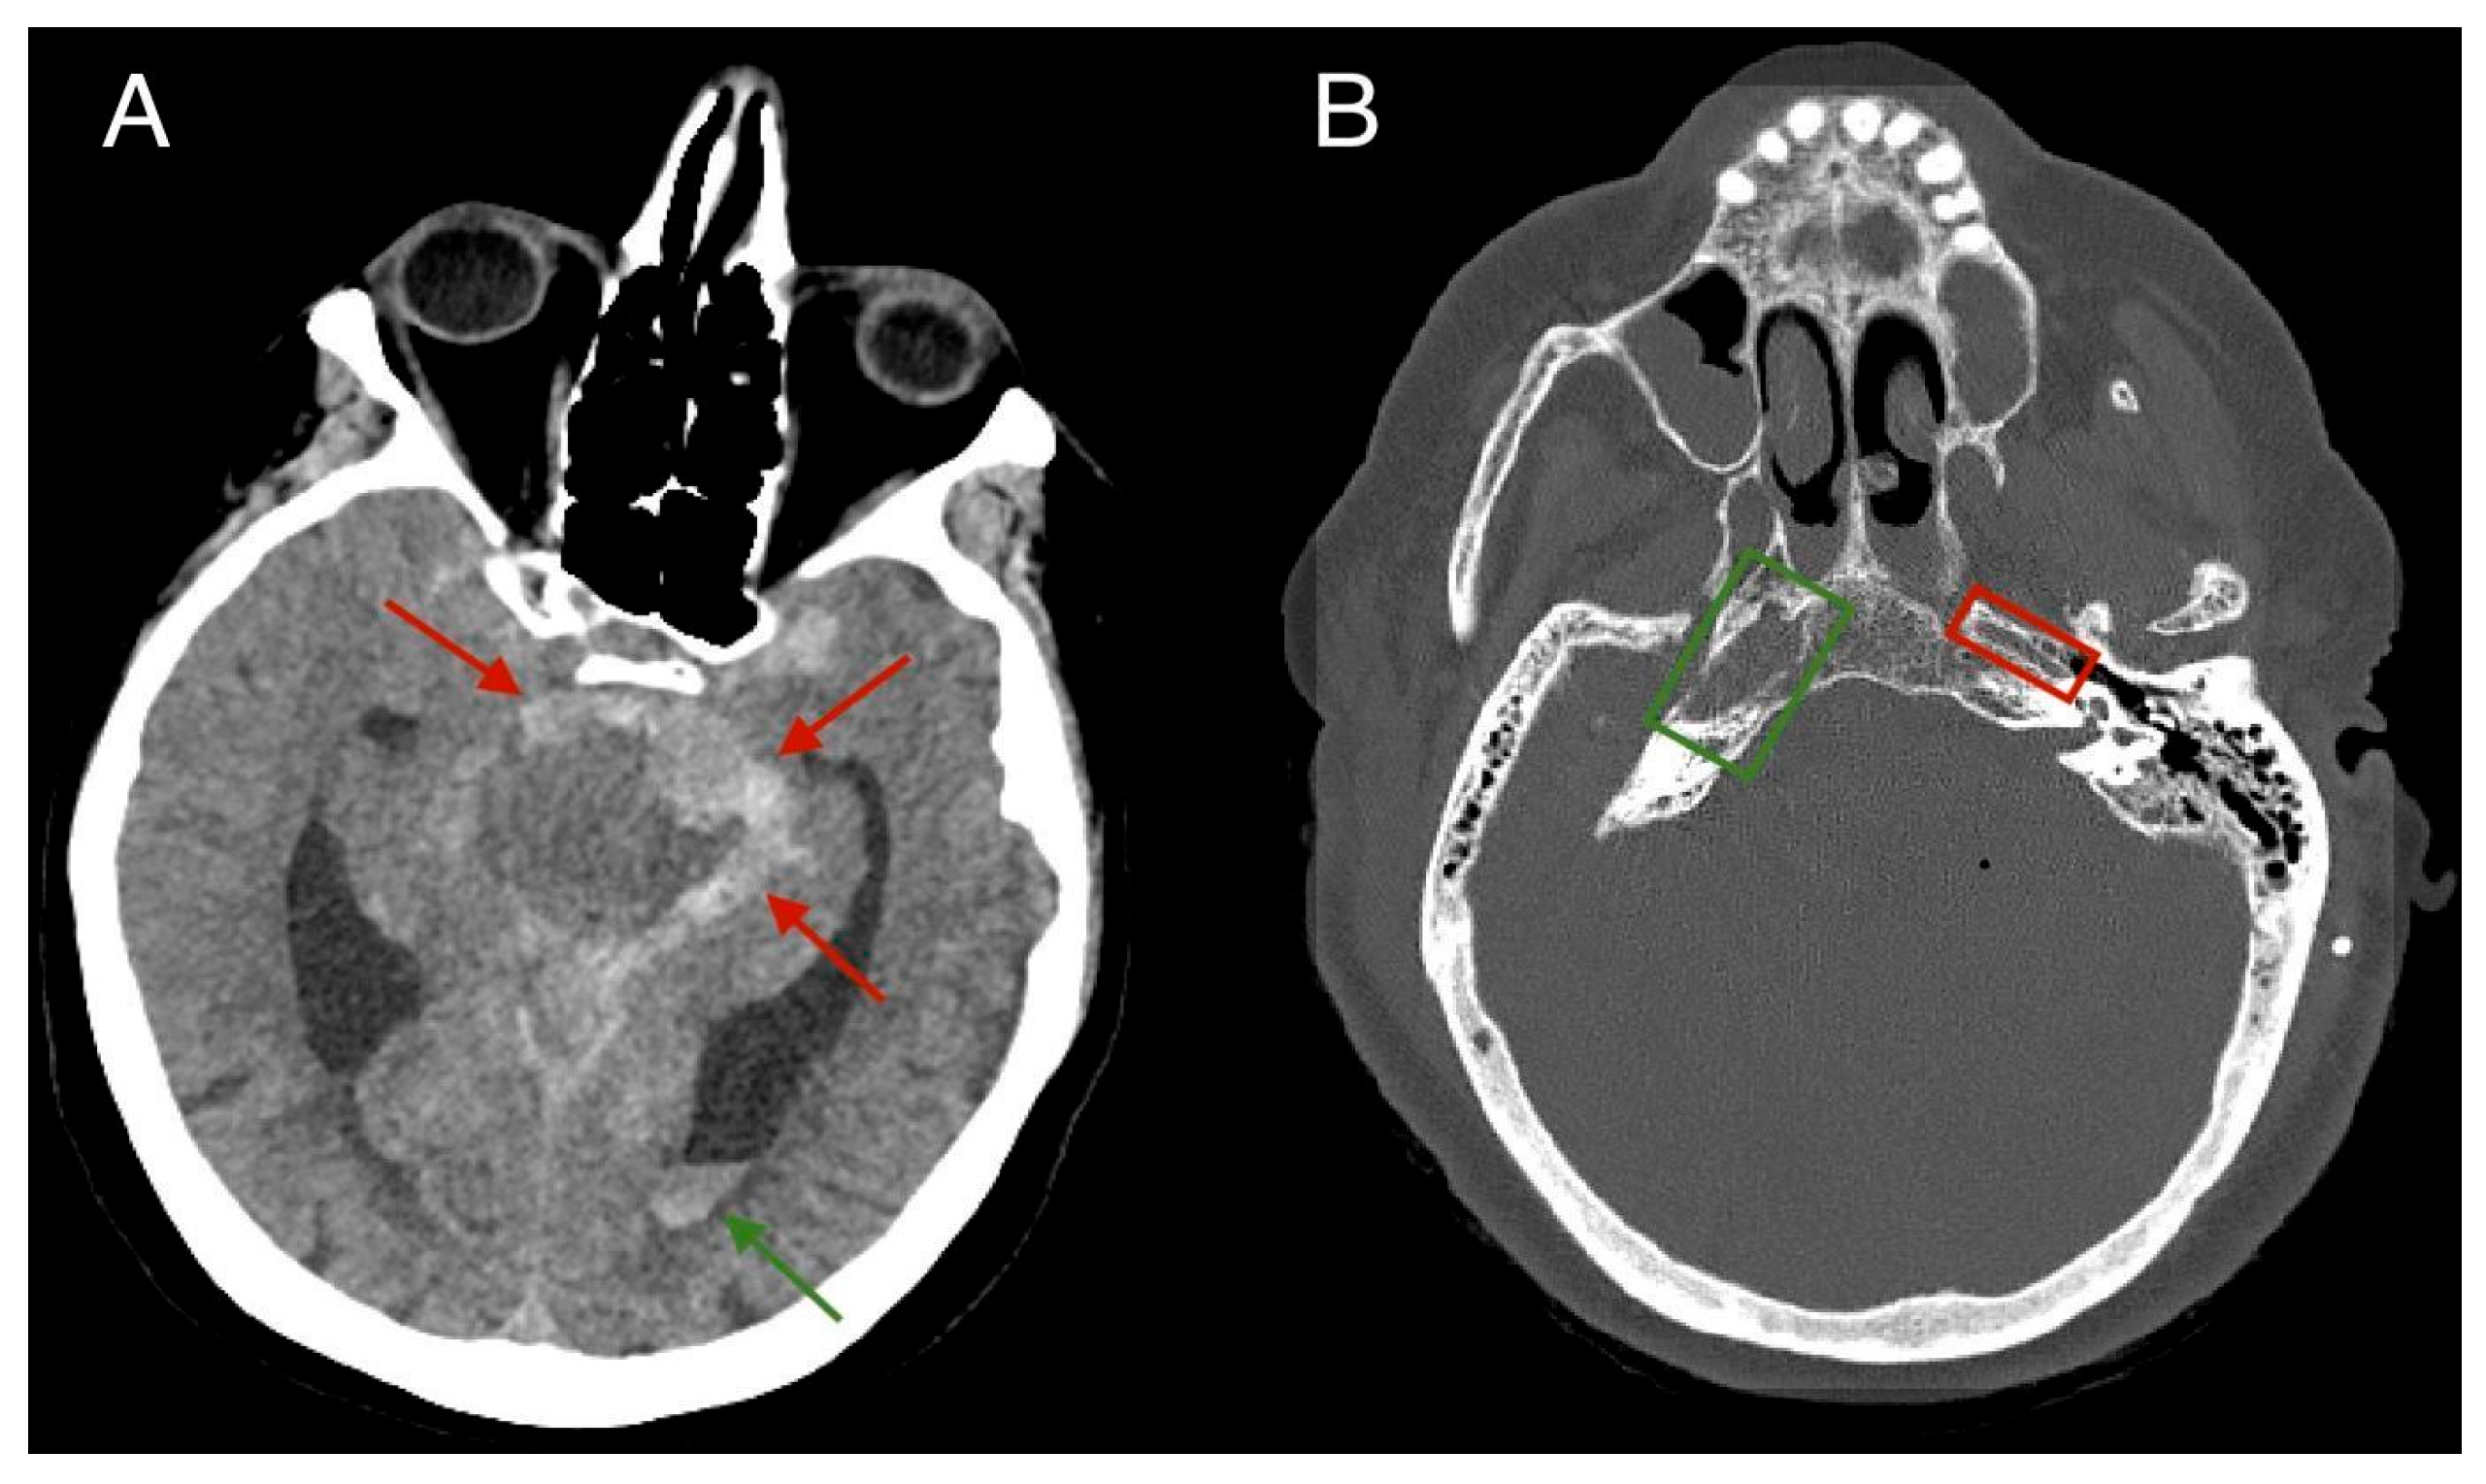

2. Case Report